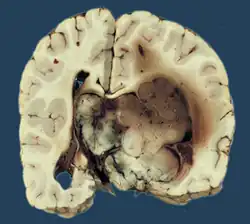

Choroid plexus papilloma, also known as papilloma of the choroid plexus, is a rare benign neuroepithelial intraventricular WHO grade I lesion found in the choroid plexus.[1] It leads to increased cerebrospinal fluid production, thus causing increased intracranial pressure and hydrocephalus.[2]

Choroid plexus tumors are divided into three categories by the World Health Organization (2016):[9] papillomas (grade I), atypical tumors (grade II), and carcinomas (grade III). Less than two mitotic figures per 10 high power fields are present in CPPs, two to five are present in atypical ones, and more than five are present in carcinomas. The tumors are visible as pink, soft, spherical lumps with erratic projections and considerable vascularity.

The tumor is neuroectodermal in origin and similar in structure to a normal choroid plexus. They may be created by epithelial cells of the choroid plexus. Papillary fronds lined by bland columnar epithelium are visible under the microscope. Normal absences include mitotic activity, nuclear pleomorphism, and necrosis.[10] Tumors have positive immunohistochemistry for cytokeratin, vimentin, podoplanin, and S-100.[11] Up to 20% of choroid plexus papilloma patients may test positive for glial fibrillary acidic protein (GFAP).[12] Studies have found that fourth ventricle cancers express more S100 than lateral ventricle tumors, and older patients (over 20 years) express more GFAP and transthyretin than younger patients.[13] Some individuals with choroid plexus papilloma have germline TP53 gene mutations, according to genetic analyses.[14] These cancers rarely exhibit nuclear p53 protein positivity. Aicardi syndrome, hypomelanosis of Ito, and 9p duplication are syndromic correlations of choroid plexus papilloma.

Micrograph of a choroid plexus papilloma. H&E stain.

Micrograph of a choroid plexus papilloma. H&E stain. -